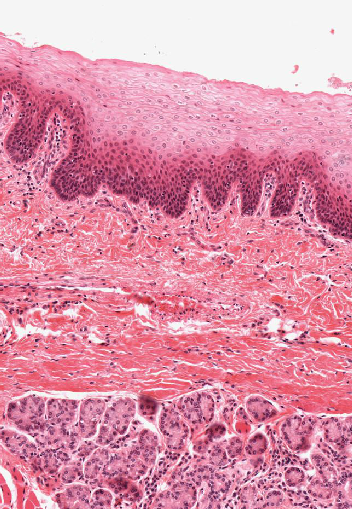

What is the arrow pointing to?

The abrupt transition between stratified squamous keratinising epithelium and non-keratinising epithelium

On the inner lip, what opens on to the surface instead of hair follicles?

Sebaceous glands (Fordyce’s spots)